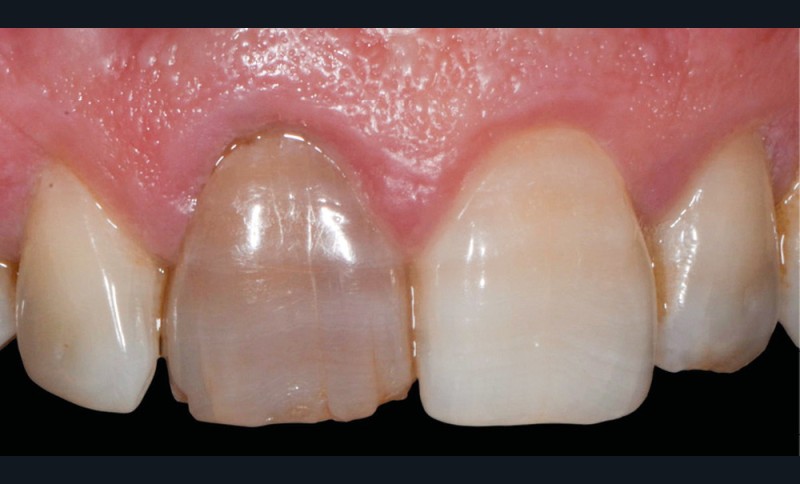

Elles intéressent la structure organo-minérale de la dent par incorporation de molécules colorées au sein du complexe amélo-dentinaire. Elles peuvent être liées à la prise de médicaments (fig. 2a), à des maladies génétiques ou congénitales. Elles peuvent également être la conséquence d’une pathologie pulpaire (fig. 2b) ou d’un acte technique (fig. 2c, d) [2, 4].